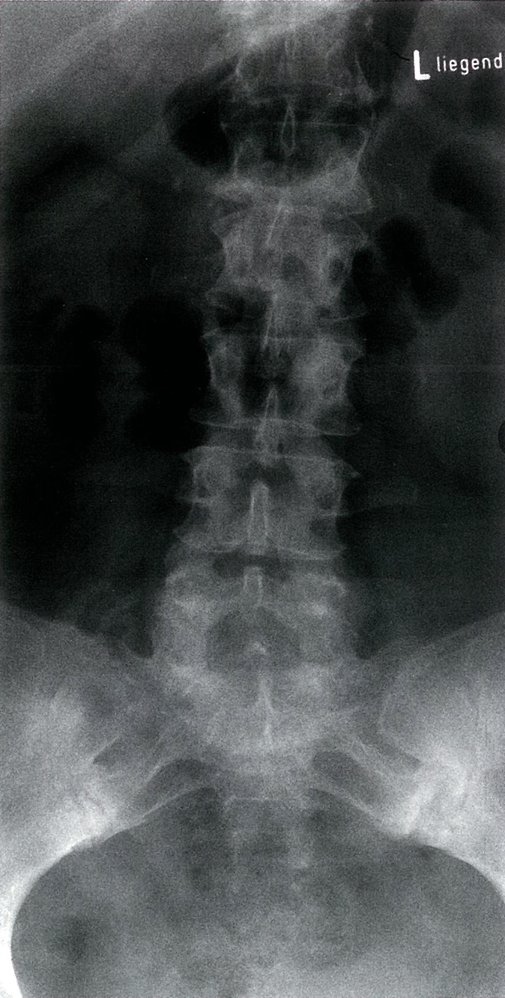

Spine (AP and lateral views)

• Characteristic findings

• Loss of lumbar lordosis: abnormal straightening of the spine

• Ankylosis of costosternal and costovertebral joints

• Dagger sign

• A radiodense line running through the center of vertebral bodies on AP view

• Caused by ossification of vertebral ligaments

• Bamboo spine: seen in later stages and is caused by the following

• Ossification of outer fibers of the annulus fibrosus resulting in ankylosis (fusion) of intervertebral joints

• Syndesmophytesbetween adjacent vertebral bodies (see “Syndesmophytes vs. osteophytes”)

• Shiny corners sign: reactive sclerosis of the superior and inferior margins of vertebrae